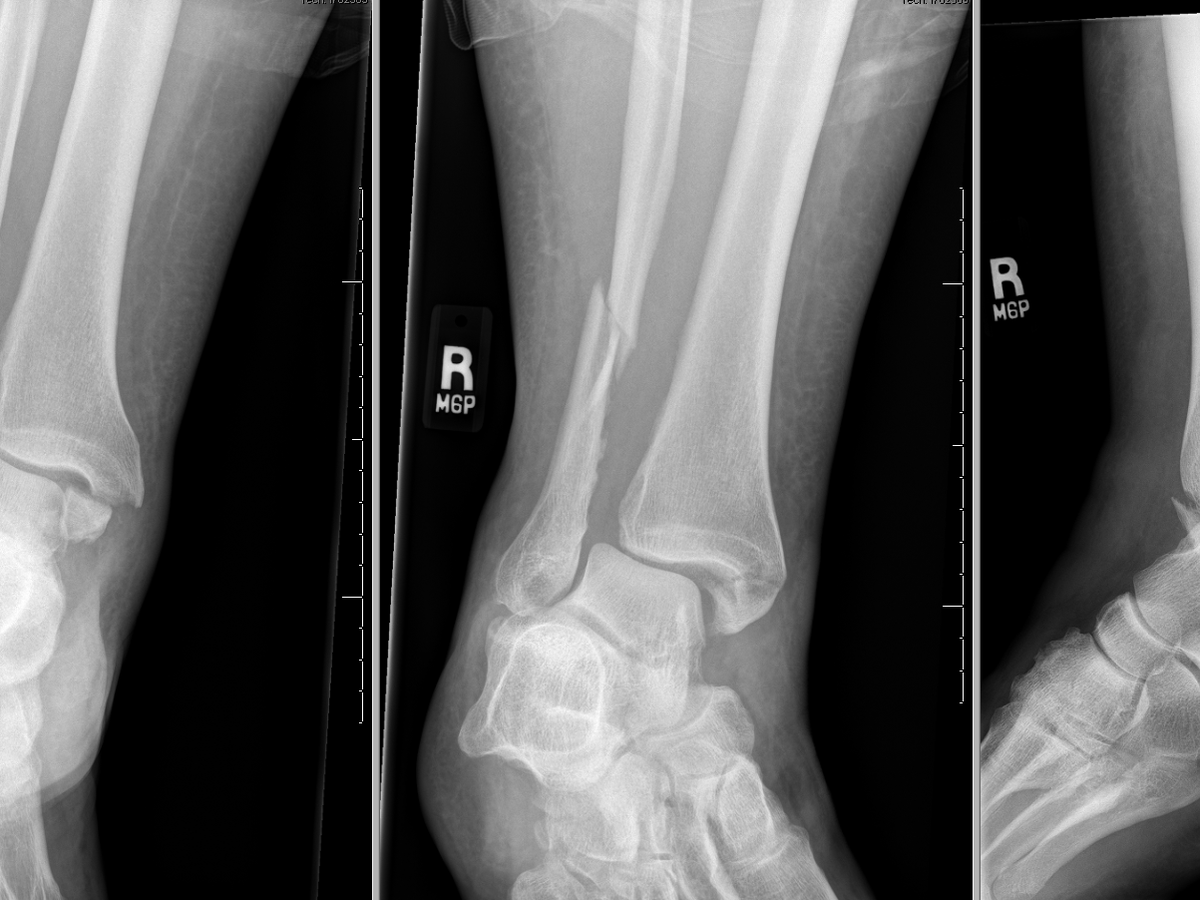

Hello, and thank you for taking the time to read this. My name is Rhena, and on February 4th, I slipped and broke both the tibia and fibula of my right leg near the ankle as I was walking to work. I have been off work since, and will be for the next few months. I am working on getting on temporary disability, but I have rent and bills coming up in a few weeks and need assistance. I greatly appreciate any help you can offer, whether it's $5 or just sharing my gofundme.